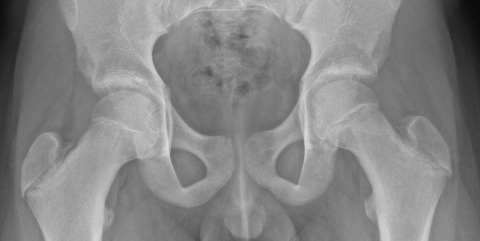

Epiphysiolyse de hanche gauche, diagnostiquée sur l’asymétrie des physes fémorales proximales et sur le terrain (adolescent en discret surpoids).